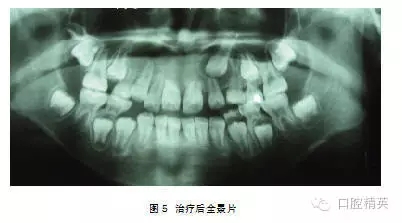

處理:行外科開窗+正畸牽引治療,6個月后破齦萌出,連續(xù)牽引,12個月后到位(圖5~7)。